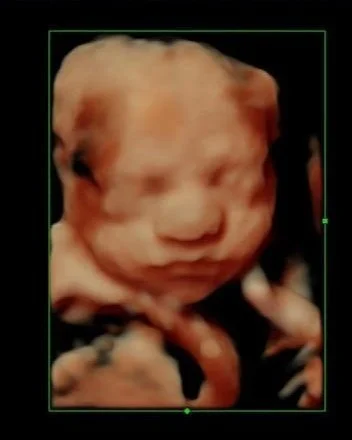

Week 27

Baby is getting so smart! Their brain is extremely active and can now distinguish different voices. You may also feel your baby hiccup from time to time, which can be an interesting sensation!